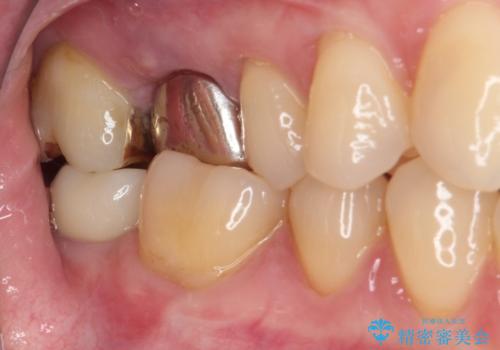

ゴールドインレーは銀歯のインレーやセラミックインレーと比べ、「技工操作の精度が高く、適合が著しく良い」というメリットがあります。特に上の奥歯は歯科医師の操作が行いにくいため、「適合の良さ」は再治療のリスクを防ぐ上でとても重要な要素となります。

上の奥歯は金属色が見えることもないため、審美的な問題は全くありません。

咬み心地はとても良好で、全く違和感がなく、患者様には大変満足していただきました。